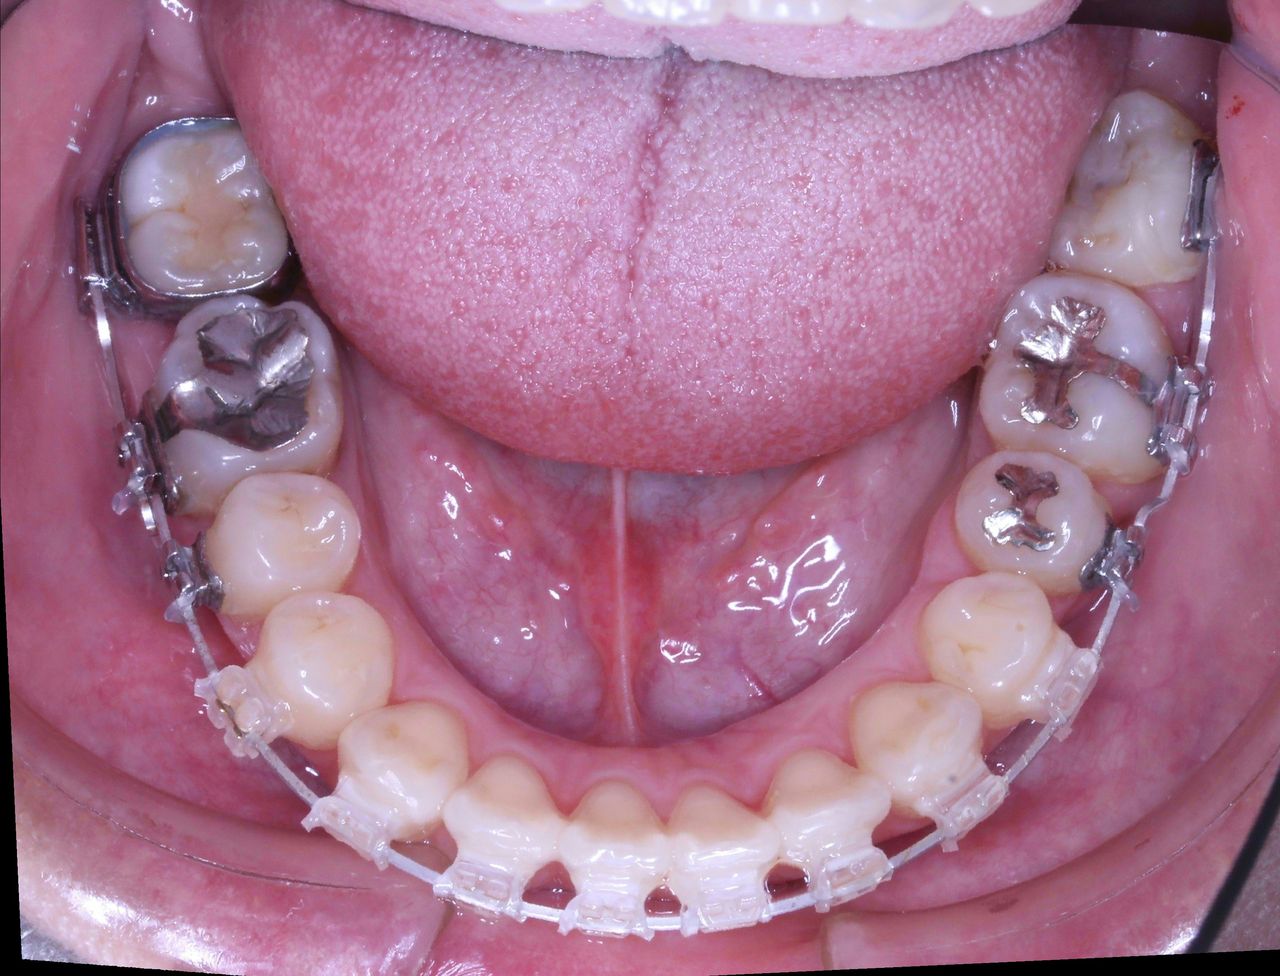

少し経過が進みました

治療開始から3年経過した現在の状況です